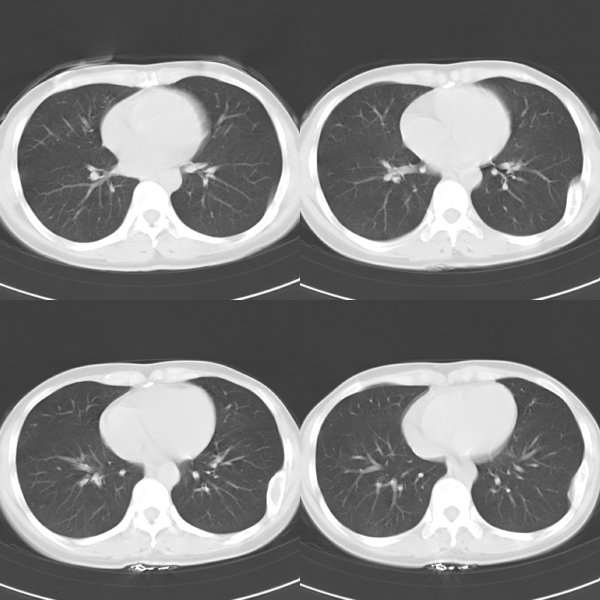

标题: CT19623:F40y,肋骨改变。

40岁女性,双侧胸部疼痛,以左侧为明显1+年。余无明显异常。

左侧肋骨单发膨胀性病变,皮质连续,病史较长,首先考虑良性病变:骨纤可能性大。